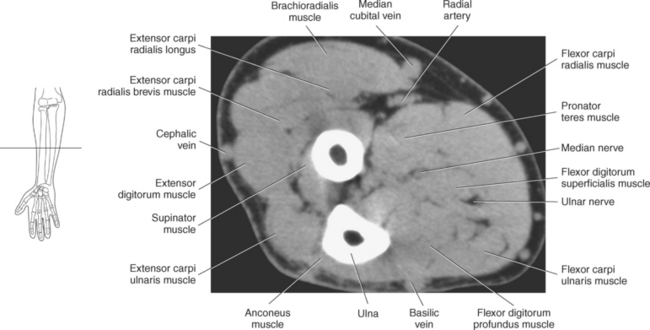

One method to classify the muscles of the forearm is to use the radius, ulna, and interosseous membrane to divide them into a ventral group (the flexors) and a dorsal group (the extensors). The two groups can be further divided into superficial and deep muscles. The muscles of the forearm are described in Table 9.5.

All five of the superficial muscles in the ventral group have an origin from the common flexor tendon off the medial epicondyle of the humerus. These muscles are demonstrated in Figures 9.86 through 9.98.

The muscles of the superficial dorsal group are demonstrated in Figures 9.87 through 9.98 and 9.100. The brachioradialis is an extensor muscle lying along the lateral border of the forearm. This large muscle arises from the upper two thirds of the supracondylar ridge of the humerus and attaches distally to the radial styloid process. The brachioradialis flexes the forearm at the elbow and assists with pronation and supination (Figure 9.100).

The brachial plexus, also described in Chapter 4, is a large network of nerves that innervate the upper limb (Figures 9.38 and 9.148). It extends from the neck into the axilla. The brachial plexus is formed by the union of the ventral rami of nerves C5-C8 and the greater part of the T1 ventral ramus. The ventral rami from C5 and C6 unite to form a superior trunk, the ventral ramus of C7 continues as the middle trunk, and the ventral rami of C8 and T1 unite to form an inferior trunk. Each of these trunks divides into an anterior and posterior division. The anterior divisions supply the anterior (flexor) parts of the upper limb, and the posterior divisions supply the posterior (extensor) parts of the upper limb. These divisions form three cords (posterior, lateral, and medial) that continue to divide to form the median, ulnar, musculocutaneous, and radial nerves (sequential Figures 9.59 through 9.67 and 9.87 through 9.95). These nerves supply the muscles of the forearm and hand. The median nerve descends the cubital fossa deep to the median cubital vein. It supplies the pronator teres muscle of the arm and all the superficial and deep flexor muscles of the forearm, except the flexor carpi ulnaris muscle. It gives off an anterior interosseous branch that descends within the forearm to supply the flexor digitorum profundus muscle. The median nerve courses through the carpal tunnel of the wrist, typically superficial to the flexor tendons (Figure 9.147). It supplies flexors of the hand, skin of the wrist, thenar eminence, palm of the hand, and sides of the first three digits and lateral half of the fourth. At the elbow, the ulnar nerve passes between the medial epicondyle of the humerus and the olecranon process within the cubital tunnel to enter the medial side of the flexor compartment of the forearm (Figure 9.148). Posterior to the medial epicondyle, the ulnar nerve is superficial and easily palpable. It supplies the flexor carpi ulnaris muscle and the medial side of the flexor digitorum profundus muscle in the forearm before entering the hand. The ulnar nerve passes under the flexor retinaculum, along with the ulnar artery, to enter the palmar compartment of the hand (Figure 9.147). At this point, the ulnar nerve divides into superficial and deep terminal branches that supply the ulnar flexors of the hand as well as the skin on the medial side of the palm, medial half of the dorsum of the hand, fifth digit, and medial half of the fourth digit. The musculocutaneous nerve descends to the lateral side of the arm and elbow to innervate the flexors in the arm and the skin of the forearm, wrist, and thenar region of the hand (Figure 9.146). It emits branches that supply both heads of the biceps brachii muscle, the brachialis muscle, and the elbow joint. It innervates the skin of the dorsal surface of the arm. A continuation of the musculocutaneous nerve is the lateral cutaneous nerve, which terminates into cutaneous branches that supply the skin covering the radial side of the wrist and the thenar eminence. The radial nerve is the largest branch of the brachial plexus. It passes inferolaterally around the body of the humerus in the radial groove (Figure 9.146). It continues inferiorly between the brachialis and brachioradialis muscles to the level of the lateral epicondyle of the humerus, where it divides into deep and superficial branches. The deep branches supply all the extensors in the arm and forearm, and the cutaneous branches innervate the skin on the dorsal side of the arm and hand. The superficial branch, the direct continuation of the radial nerve, is entirely sensory. It supplies skin and fascia over the lateral two thirds of the dorsum of the hand, the dorsum of the thumb, and proximal parts of the lateral three and one half digits on their dorsal surfaces (Figures 9.57 through 9.67, 9.87 through 9.98, and 9.146 and 9.147).